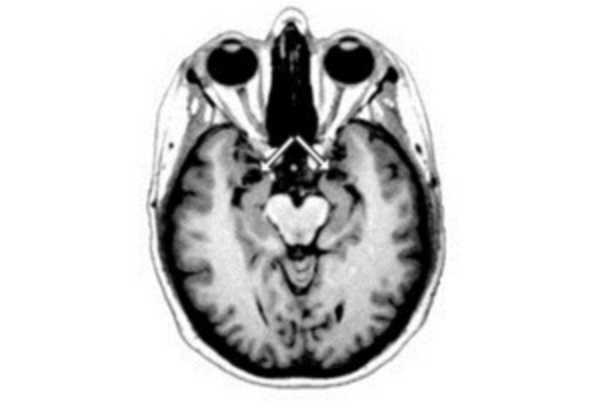

Биологи проследили за развитием мозга мыши с 15-го дня с момента зачатия, отслеживая все изменения в работе генов, происходившие по мере взросления. Особое внимание уделялось тем участкам генома, которые ранее связывались с развитием шизофрении, аутизма или других психических расстройств.

В ходе исследования ученые заметили, что гены аутизма и шизофрении были активны только на ранних этапах развития зародыша и во время первых дней жизни мышат.